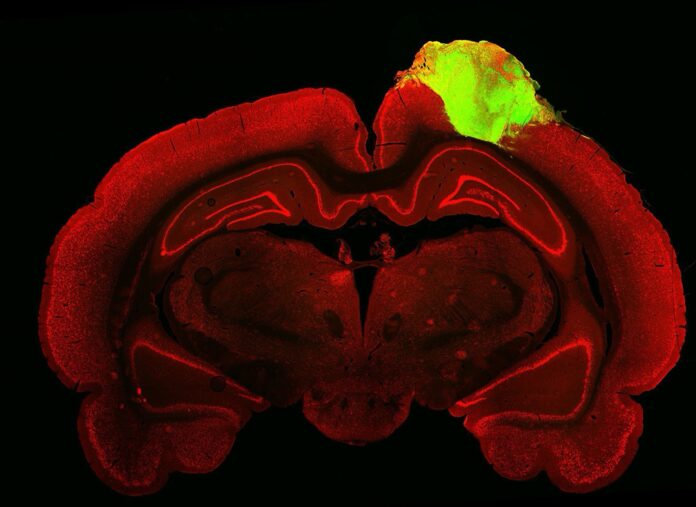

Laboratuvarda yetiştirilen beyin hücreleri iki ya da üç günlük farelere nakledildi.

Yetişkin farelerdeki geçmiş denemelerin aksine, yeni çalışmada beyin hücreleri hızla emildi ve altı ay sonra beynin üçte birini oluşturarak farelerin karar verme ve fiziksel tepkilerinin bir parçası haline geldi.